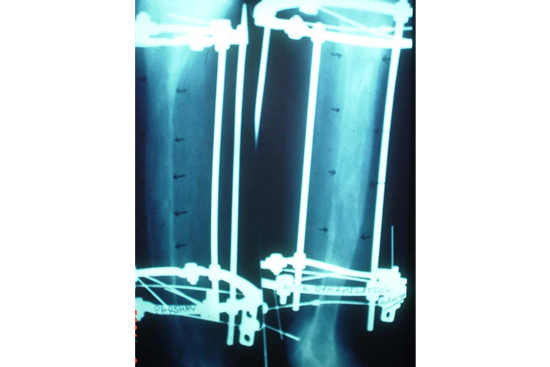

Limb Lengthening